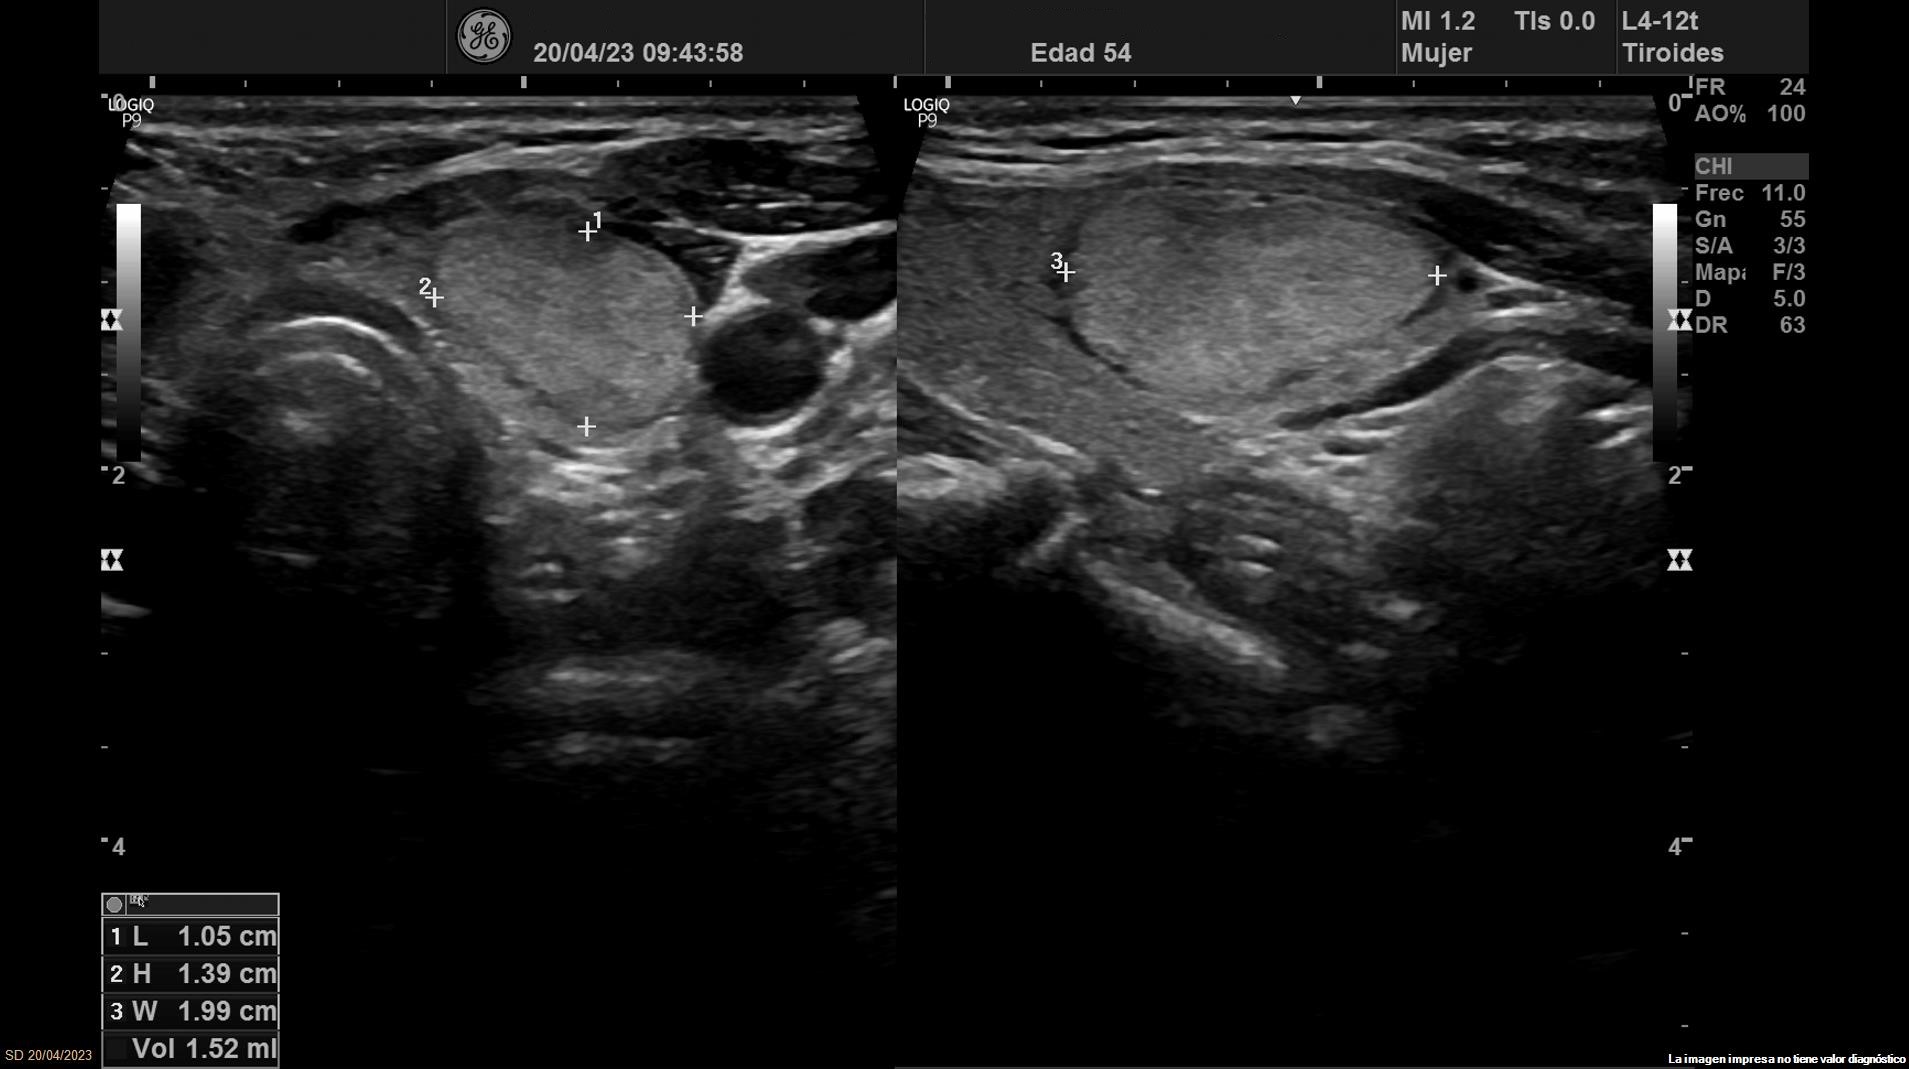

• Lóbulo tiroideo izquierdo: tamaño normal. En la mitad inferior se objetiva un nódulo de 11 x 14 x 20 mm (Vol 1,52 ml), bien definido, sólido e iso/hiperecoico, con halo fino hipoecoico, sin calcio y con vascularización de predominio periférico (ATA: baja sospecha).